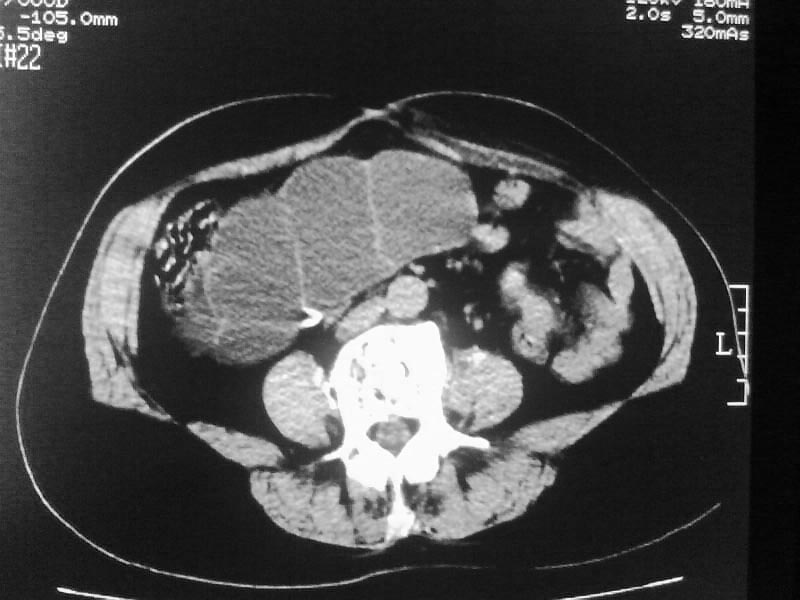

标题: CT20044:女,45岁,腰痛2年,双肾结石,右输尿管结石,右肾重度积 [打印本页]

标题: CT20044:女,45岁,腰痛2年,双肾结石,右输尿管结石,右肾重度积

双肾结石、双输尿管结石并右肾积水。

双肾,输尿管结石,右肾重度积水。